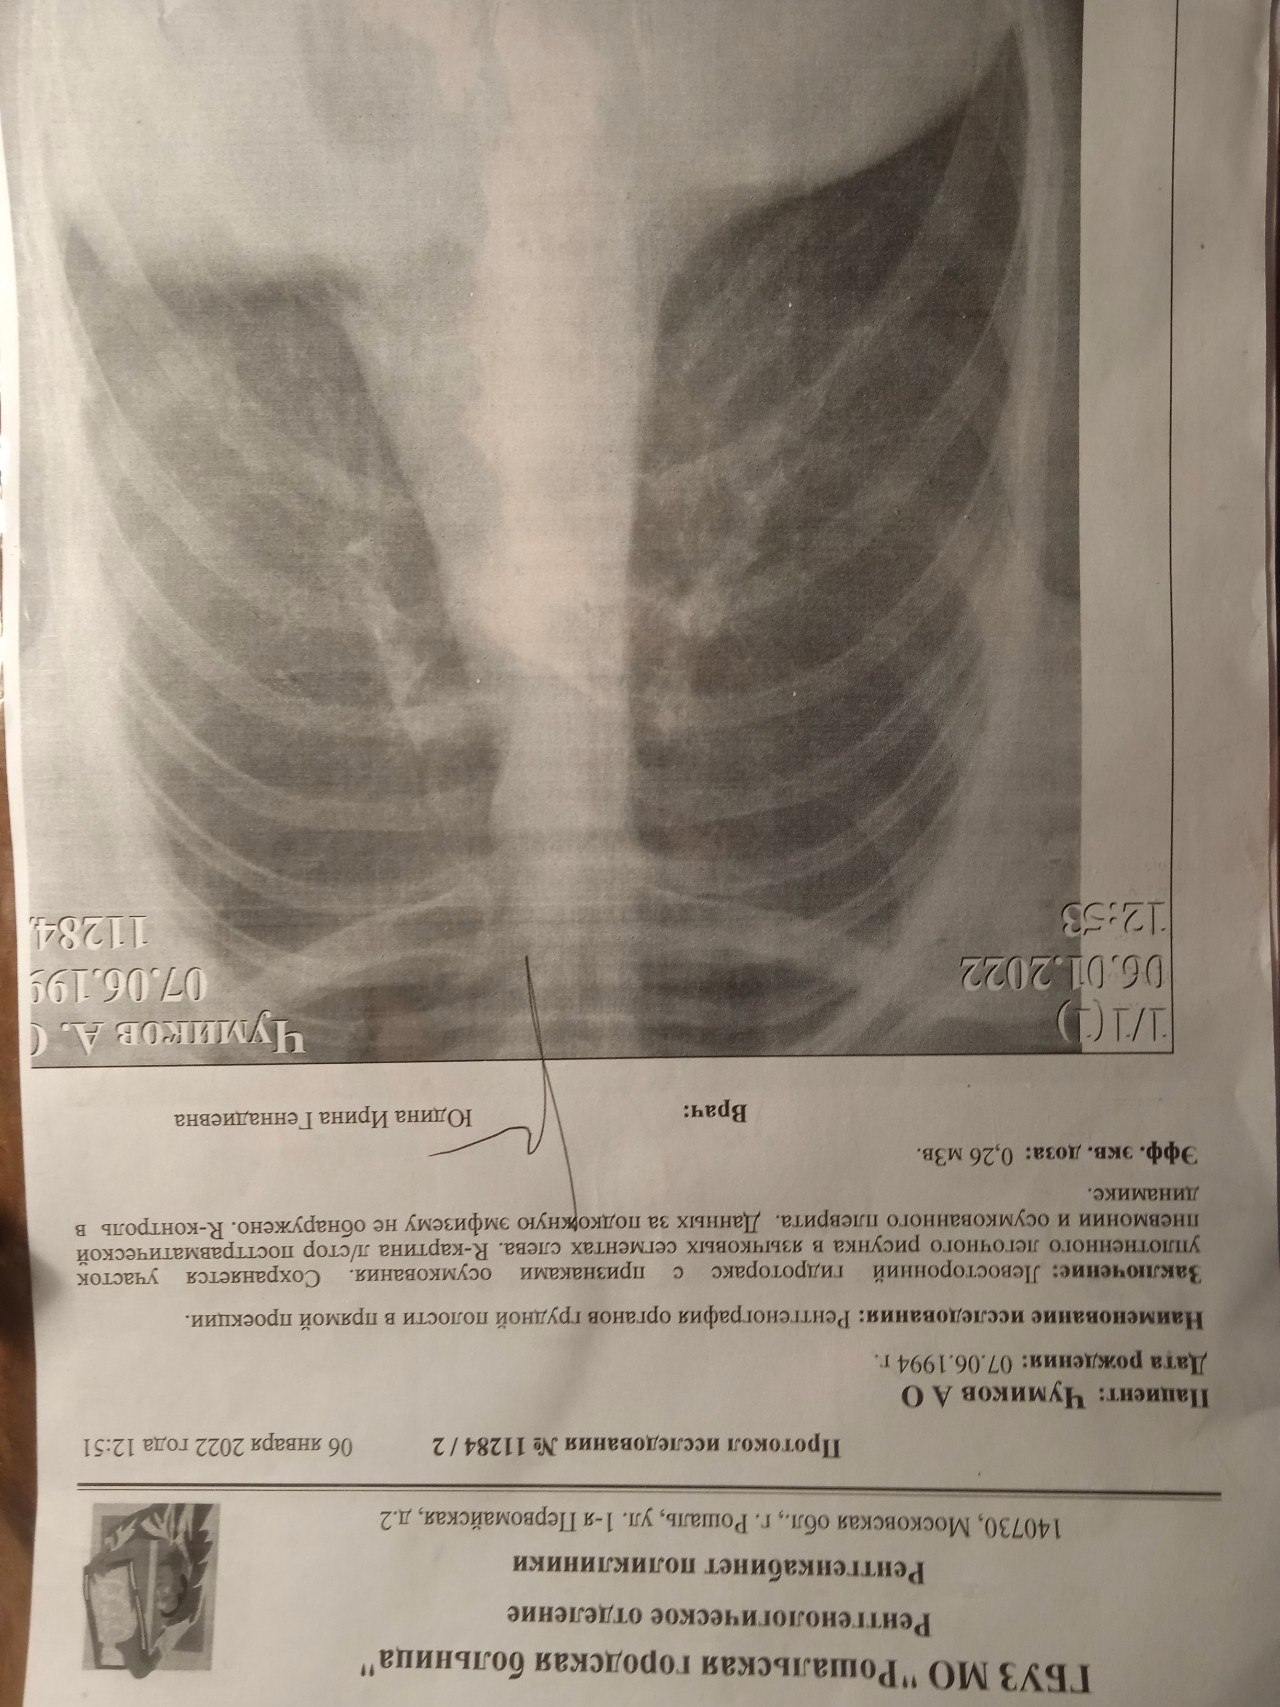

Что такое малоконтрастная рентгенограмма органов грудной клетки